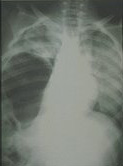

Multiple thoracoabdominal injury, haziness and blunting of costodiaphragmatic recess indicating the hemothorax.

Plain chest X-ray finding of ruptured diaphragm. The bowel gas pattern is noted in the right hemithorax